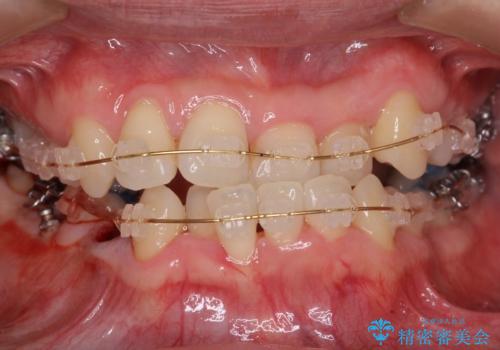

- 矯正装置

- 審美装置

- 受け口を主訴に来院。

下あごが大きく、顎の手術を含めた矯正をおすすめしましたが、手術は怖いので絶対にしたくないとのことでした。

歯並びのみを治す矯正は難しく、長期にわたる治療になるとご説明しました。

かみしめもあり、骨も固く、歯根も長いためなかなか歯が動かず、患者様も治療する側も忍耐を要する長期戦となりました。